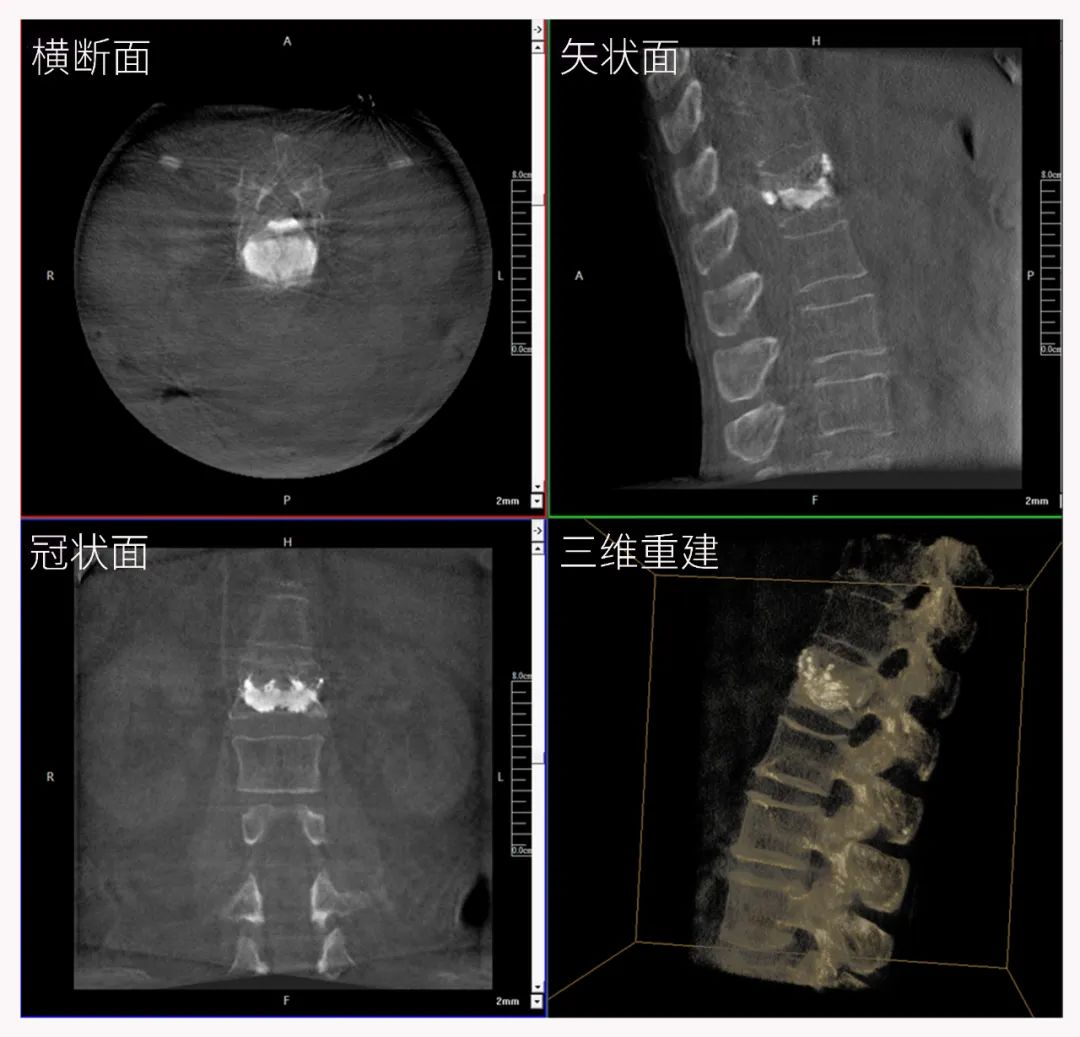

三維C形臂也被稱為“術(shù)中CT”,它具備二維C形臂的全部功能。此外,它還具備三維成像功能,三維C形臂旋轉(zhuǎn)采集多角度的二維投影數(shù)據(jù),再通過計算機進行三維重建,能夠生成橫斷面、矢狀面、冠狀面斷層圖像以及三維立體圖像,提供更全面、更立體的解剖學(xué)信息。

三維“類CT”影像

三維切面影像可以看出病灶點

二維C形臂提供的影像存在固有局限性,其成像原理是基于單一方位的投影,導(dǎo)致深部解剖結(jié)構(gòu)信息缺失,且容易受到骨骼和組織的重疊干擾,使得部分病灶難以清晰顯示,甚至被掩蓋。相比之下,三維C形臂通過三維重建技術(shù),可以獲得類似CT的斷層掃描圖像,從而解決了二維影像的重疊問題。

醫(yī)生能夠利用這些三維圖像,更直觀、更深入地分析病變,進行全方位觀察,例如:精確評估骨折復(fù)位情況、清晰顯示內(nèi)植入物的位置及其與周圍組織的關(guān)系等。尤其在復(fù)雜骨折、脊柱手術(shù)、呼吸介入等臨床場景中,三維C形臂提供的詳細(xì)信息對手術(shù)導(dǎo)航和療效評估至關(guān)重要。